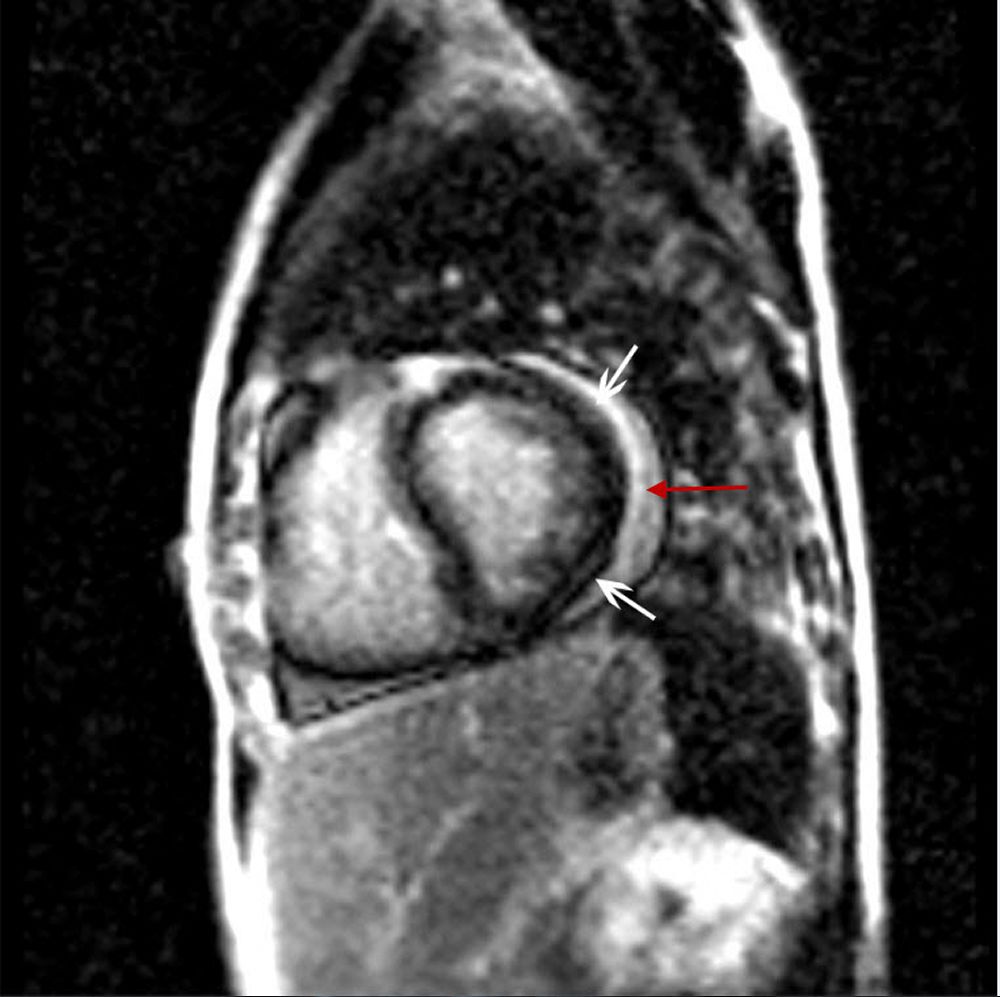

Un attacco cardiaco è la morte del tessuto cardiaco